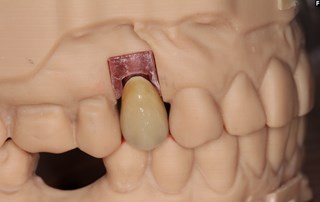

Färdig krona

Kronan klar för montering i munnen